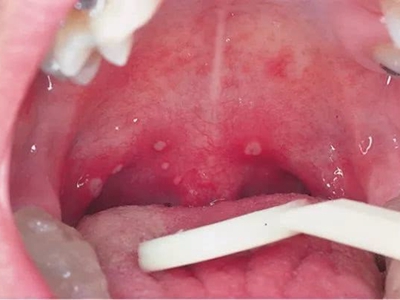

咽峡

充血 · 红斑

小儿疱疹性咽峡炎最早期图

小儿疱疹性咽峡炎最早期,上腭、咽部黏膜会出现红肿、充血,表面为大片红斑,随着疾病进展,红斑上会出现数量不等的小疱,伴有疼痛不适感。